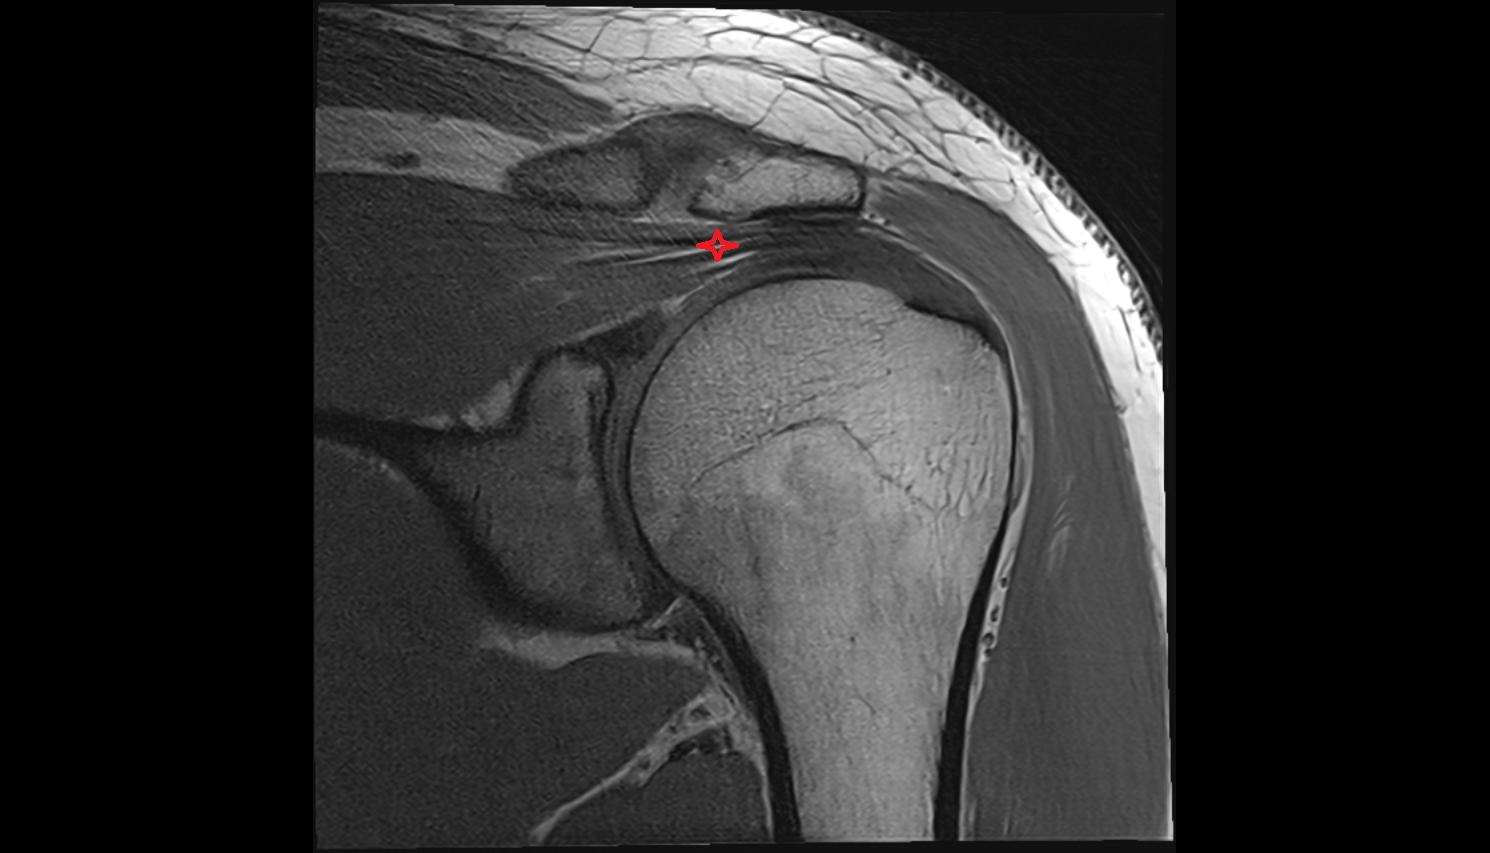

- Supraspinatus tendon